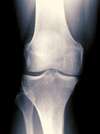

L’os de la cuisse (le fémur) s’articule avec l’os principal de la jambe (le tibia) au niveau du genou. Les surfaces osseuses en contact en mouvement lors de la marche, sont recouvertes d’un revêtement élastique, souple (le cartilage) chargé de faciliter leur glissement.

Lorsque cette structure s’use puis disparaît (on parle alors d’arthrose), l’os se retrouve à découvert dans l’articulation et lors de la marche, l’os du fémur rentre en contact avec l’os du tibia. Cela entraîne des frottements « os sur os » lors des mouvements du genou, ce qui provoque de l’inflammation avec douleur, gonflement du genou puis enraidissement.

L'usure commence là où l’articulation travaille le plus. Selon la forme de la jambe, l’un ou l’autre des compartiments du genou supporte plus le poids du corps que les autres et va donc s’user prématurément.